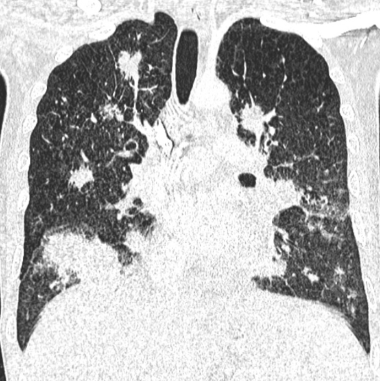

Général

- Patients HIV <200 CD4++ ou Patients Transplantés ++

- Condensations nodulaires mal définies, “en flamme”

- Péribronchovasculaire

- DD: Lymphome lié au SIDA (2e plus fréquent)

kaoposi aids sida vih hiv lung poumon poumons thorax thoracique sarcoma